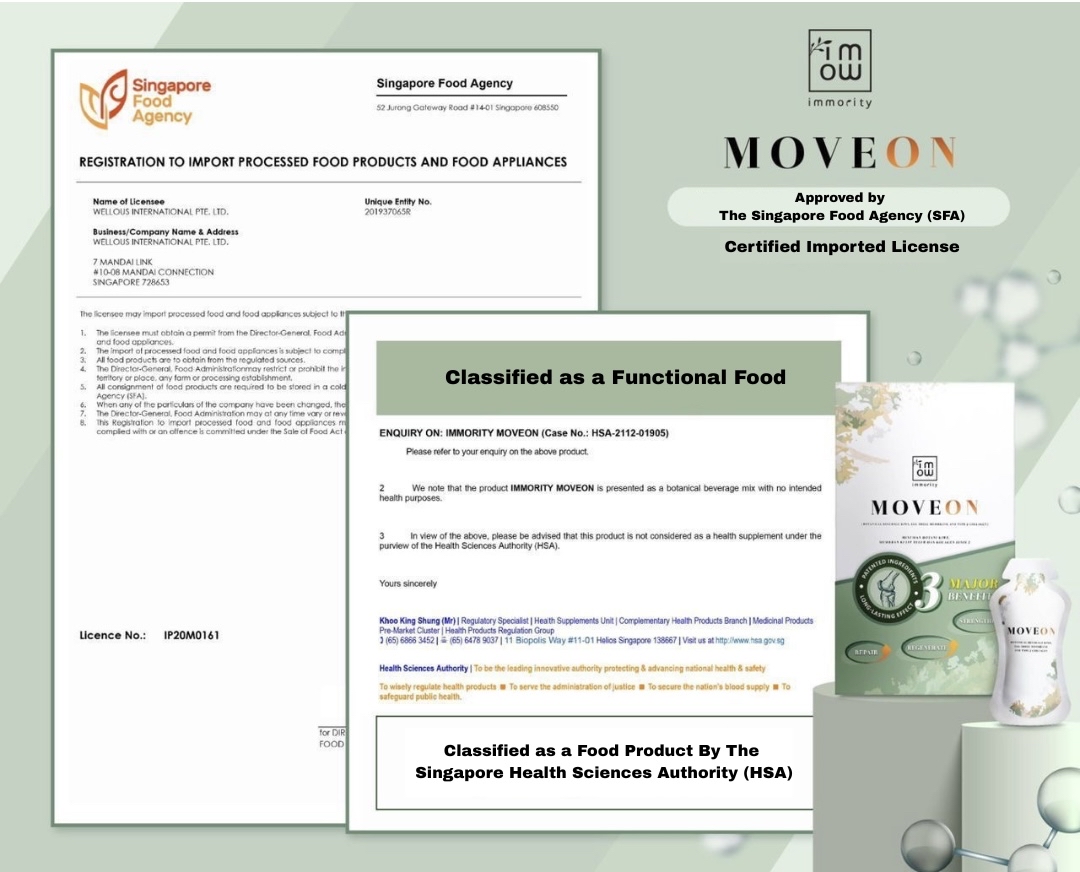

Approved by HSA& SFA, Trusted by 50,000 Singaporeans

100% Safe & Natural. 33 Years Of R&D, Approved by HSA, SFA, SGS, MOH & HALAL certified.

- Certified HALAL, HSA, SFA, USA FDA

Moveon Liveon is made from 100% natural ingredients, free from steroids, chemicals, or side effects. They are certified by HSA, SFA, HALAL, and USA FDA, and are safe for long-term use with no known side effects.